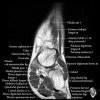

- Axial section

Axial PD fat suppression evaluates the tendons and ligaments of the ankle particularly after acute/subacute injuries. It also is sensitive to talar dome osteochondral defects. Alternatively, a T2 sequence can be used to eliminate magic angle artifact that may occur as the tendons travel around the malleolar turns.

Tibiofibular ligaments

Lateral ankle ligaments

Deltoid and spling ligaments

Tendon(Achilles, Medial, Lateral, Anterior)